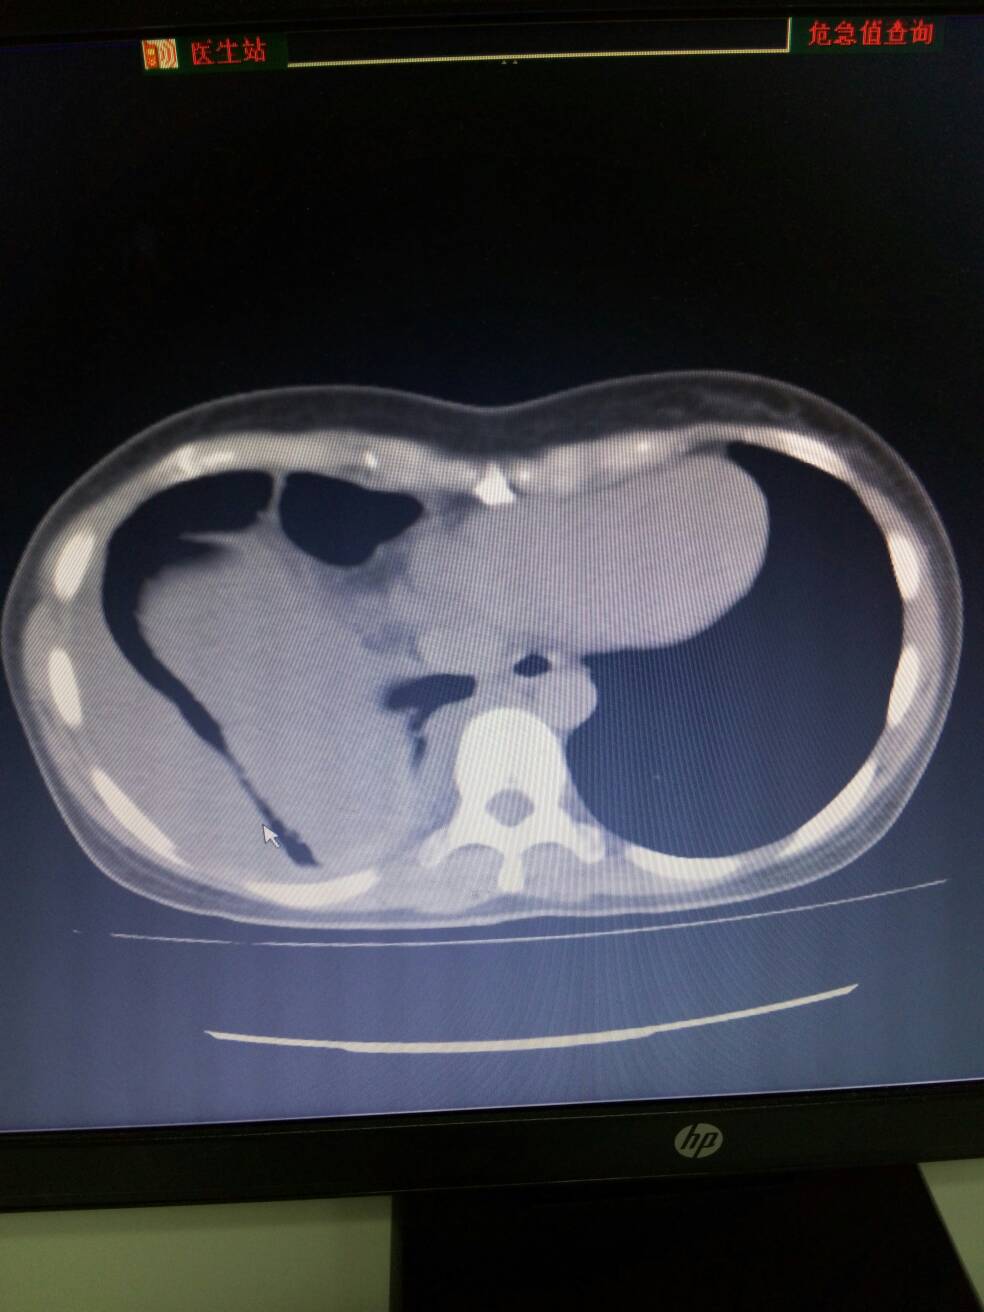

右侧结核性胸膜炎,部分包裹。右下肺部分膨张不全。

结核性胸膜炎